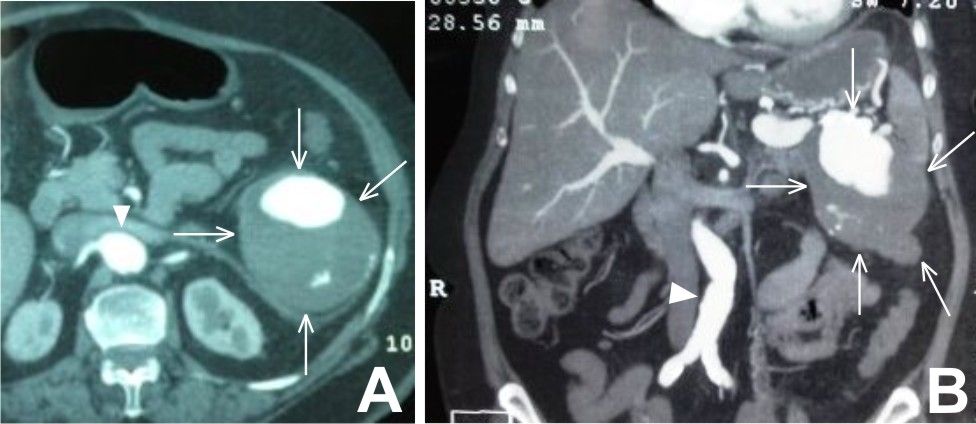

Excelente artigo publicado em abril de 2016 abordando aneurismas viscerais.

Os autores fazem uma revisão sobre o assunto e diagnóstico e dão seis dicas de abordagens terapêuticas.